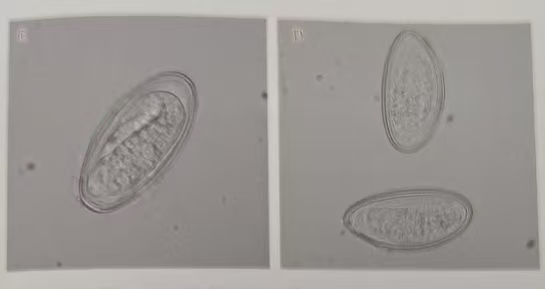

实验室工作人员在显微镜下可观察到具有体型细长如线,尾部尖直、头端两侧角皮膨大呈翼状透明结构的成虫,及大量无色透明,两侧不对称椭圆形虫卵。(如图1,2)

图2显微镜下蛲虫虫卵(实拍未染色×400)

图4 蛲虫虫卵显微镜下形态 未染色×400(体液肿瘤细胞形态学与寄生虫图谱)